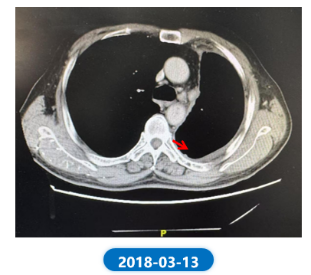

• 2018.03.13 复查CT:同前比较,左肺病灶及胸膜转移,较前进一步退缩;其余变化不大。

肺“长”实“例” :从真实世界病例看EGFR ex20ins NSCLC患者综合治疗模式下的长生存漫漫路732.png